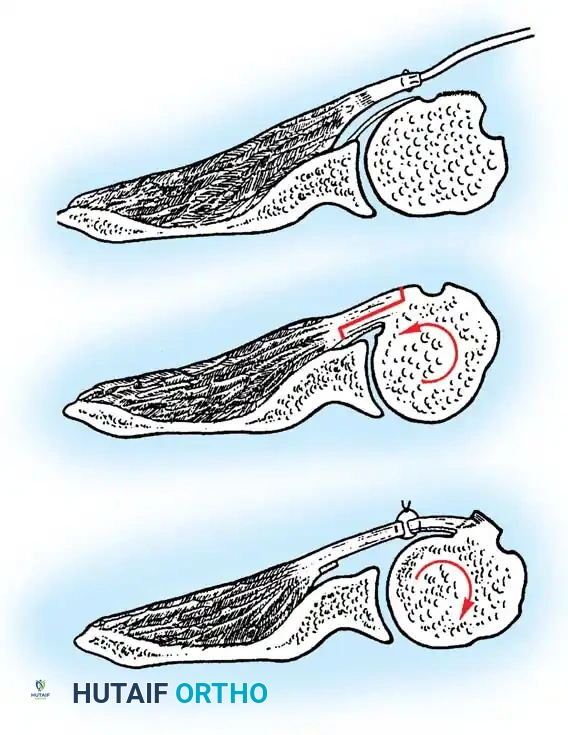

2. Subscapularis Management

The subscapularis is the gatekeeper to the joint. It can be managed via a tenotomy (1 cm medial to the lesser tuberosity), a lesser tuberosity osteotomy (LTO), or a subscapularis peel. LTO provides superior bone-to-bone healing and is increasingly favored.

Broach the humeral canal sequentially. Assess the trial components for stability, ensuring 50% posterior translation on the "drawer test" and no superior escape. Implant the final prosthesis (press-fit or cemented based on bone quality).

Securely repair the subscapularis using heavy non-absorbable sutures through transosseous tunnels.